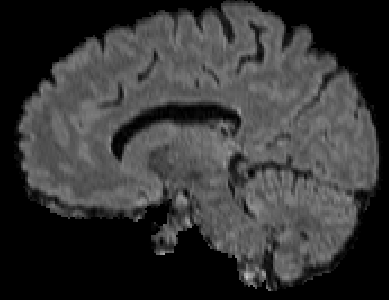

Recently, segmentation methods based on Convolutional Neural Networks (CNNs) showed promising performance in automatic Multiple Sclerosis (MS) lesions segmentation. These techniques have even outperformed human experts in controlled evaluation conditions such as Longitudinal MS Lesion Segmentation Challenge (ISBI Challenge). However state-of-the-art approaches trained to perform well on highly-controlled datasets fail to generalize on clinical data from unseen datasets. Instead of proposing another improvement of the segmentation accuracy, we propose a novel method robust to domain shift and performing well on unseen datasets, called DeepLesionBrain (DLB). This generalization property results from three main contributions. First, DLB is based on a large group of compact 3D CNNs. This spatially distributed strategy ensures a robust prediction despite the risk of generalization failure of some individual networks. Second, DLB includes a new image quality data augmentation to reduce dependency to training data specificity (e.g., acquisition protocol). Finally, to learn a more generalizable representation of MS lesions, we propose a hierarchical specialization learning (HSL). HSL is performed by pre-training a generic network over the whole brain, before using its weights as initialization to locally specialized networks. By this end, DLB learns both generic features extracted at global image level and specific features extracted at local image level. DLB generalization was validated in cross-dataset experiments on MSSEG'16, ISBI challenge, and in-house datasets. During experiments, DLB showed higher segmentation accuracy, better segmentation consistency and greater generalization performance compared to state-of-the-art methods. Therefore, DLB offers a robust framework well-suited for clinical practice.